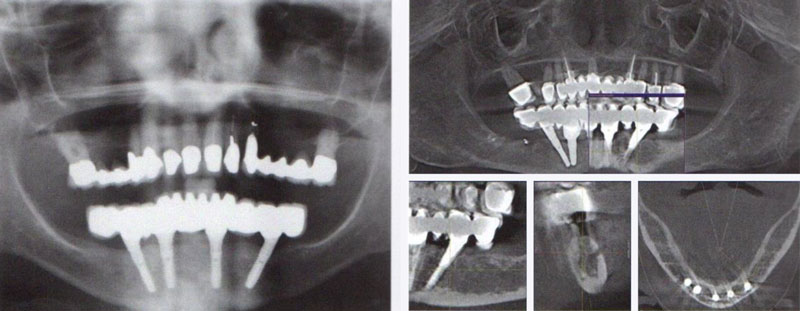

4. 從力學的角度來看,所有的種植必須符合力學上的 Ante's low。種植體的顆數和粗細千萬不要過少,以免得不償失。

5. 有關於發音問題:種植體必須要在可用的齒槽脊和適當的舌頭放置的位置尋求一個平衡點。並且考慮顳顎關節正確的休息位置,以及他咬合水平差距。

6. 有關下眼臉的問題:全口種植的病人常常會造成治療完成後的一種錯誤印象;水平線的不平衡,那就是他的嚴重的下眼瞼萎縮,造成法令紋加深;嘴唇、下巴的不對稱,造成齒列排列看起來跟嘴唇不協調。必須要術前先溝通,然後才能夠讓病人知道客觀條件是什麼!另一方面也可以用生長因子來做下眼瞼這些萎縮組織的充填跟回春。